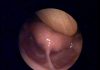

Kulakta sıvı birikmesi eğer uzun süreli kulağımızda kalırsa; Evet kulağımızda işitme kaybı yapabilir. İlk etapta bu geçici bir işitme kaybıdır. Ne kadar bir süreyle? 6 ay – 1 sene kadar eğer kulağımızda sıvı ciddi anlamda kalırsa yani hiç gerilememek üzere sürekli kulağımızda sıvı olursa ve bu sıvı birazcık sıvı olmaktan pelteleşmeye doğru giderse o zaman “İletim Tipi İşitme Kaybı” dediğimiz yani seslerin dışarıdan kulak iç kulağa doğru ilerlemesini önlediği için bir işitme kaybı oluşur. Bu işitme kaybı genelde içerideki sıvının boşaltılması ile geri döner ve hiç bir sıkıntı yaşanmaz.

Fakat bu sıvı; kulak içindeki sıvı eğer biraz pelteleşirse, içeride uzun süre kalırsa; ne kadar bu süre 6 ay ile 1 sene eğer bu kadar uzun süre kalırsa %5 ile %10 arasında “Sinirsel İşitme Kayıpları”’na yol açmaktadır. Bu bağlamda eğer kulağımızda, çocuğumuzun kulağında böyle bir problem varsa mutlaka ve mutlaka Kulak-Burun-Boğaz hekimine danışılmalı ve konu ile ilgili gerekli müdahaleler yapılmalıdır. İhmal, burada hiç hoşumuza gitmeyecek işitme kayıplarına yol açabilir.